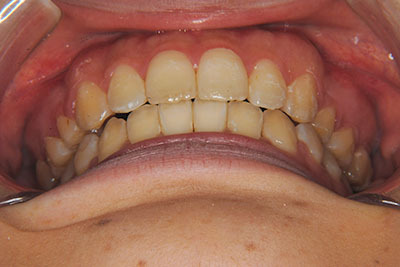

おとなの方でも矯正治療をあきらめないでください!

矯正歯科治療は子供の頃だけしかできない……

子供の頃に比べ大人になったら治療期間がすごく長い……

というようなイメージをお持ちではありませんか?

子供の頃に矯正治療を行う方が治療期間が短く済むというのは、確かですが、矯正治療は患者様の意識も重要です。

いくら歯が動き易くとも、本人がやる気でなければ効果は出ませんし、むし歯発生のリスクも高まります。おとなの方は顎の成長が終わっているため、治療の計画が立てやすいとも言えます。「もう大人だから…」とあきらめず、一度ご相談ください。